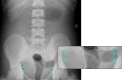

Objective: The aim of this study is to evaluate the dose reduction and image quality from implementation of Silicone Rubber-Lead (SR-Pb) as an alternative gonad shield in digital radiography (DR).

Material and methods: In this experimental study, the SR-Pb gonad shields with various thicknesses of 2, 4, 6, 8, and 10 mm were synthesized. This study used the Pb percentage of 5 wt%. An anthropomorphic phantom was used in abdomen plain examinations. The results obtained from the use of the SR-Pb was compared with standard gonad shield, i.e. lead apron. To measure the dose reduction, the Piranha detector was used. The image quality assessment was evaluated with the signal-to-noise ratio (SNR) and the contrast-to-noise ratio (CNR).

Results: This study showed the dose reduction was significant for all SR-Pb thicknesses, and incrementally increased with the increase of the SR-Pb thickness. The minimum and maximum of dose reduction were 22.8% for 2 mm and 66.9% for 10 mm SR-Pb, respectively.

Conclusion: Compared to the reference image without gonad shield, the SNR and CNR do not significantly change. Hence, the SR-Pb is probably to be used as an alternative gonad shield.